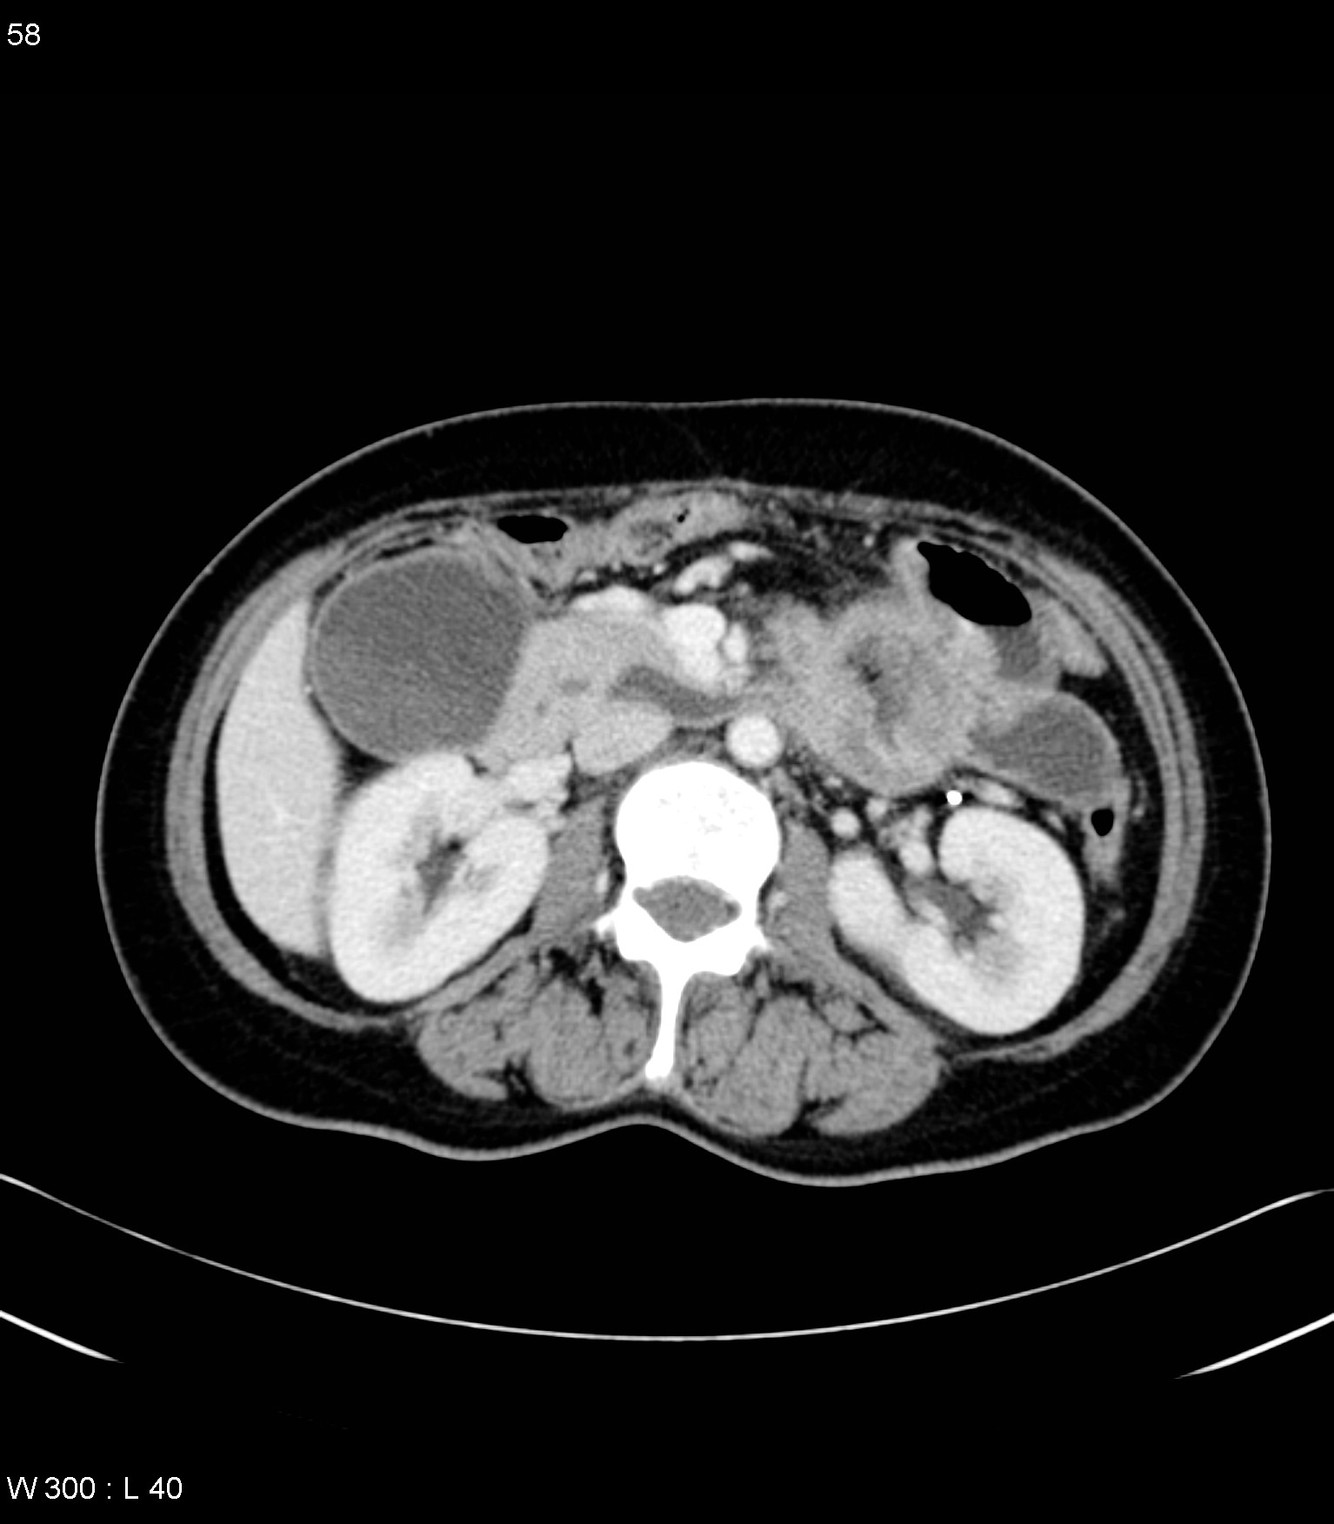

CT of the abdomen demonstrates a mass arising from the greater curvature of the body of the stomach. It is centrally ulcerated with locules of gas and contrast seen within it, but without evidence of perforation. It is a focal abnormality with thick heaped-up shoulders.

At the splenic hilum there appears to be an enlarged lymph node (this should be confirmed on thin slice and coronal reformats). No convincing evidence of metastatic disease.

The left kidney is atrophic and contains a number of what appear to be hyperdense cysts (which should be confirmed on ultrasound). The right kidney has a large simple cyst.

This patient went on to have a total gastrectomy after the stomach tumour was identified on gastroscopy.